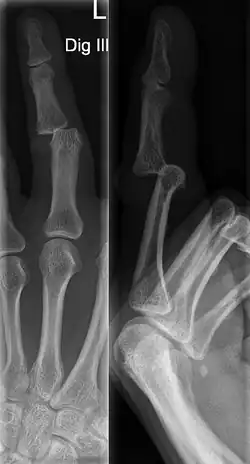

Diagnosis

A jammed finger can generally be diagnosed by a physical examination. Bone or joint deformity may indicate potential dislocations or fractures.[6] The basic structure of the finger includes three bones with joints in between each.[9] The joint closest to the tip is the distal interphalangeal (DIP) joint. The next joint, moving closer to the hand, is the proximal interphalangeal (PIP) joint. The thumb differs by only having two bones and one interphalangeal joint.[10]

The injured finger may be examined to determine where the pain is worst.[3] If the finger is sprained or dislocated, pain will be worse at the joint rather than the bone.[3] Due to the risk of dislocations or fractures, X-rays should be conducted prior to testing joint stability. This allows for prior detection of a dislocation or fracture.[3] It is recommended that a variety of views (lateral, oblique, and anteroposterior) are observed.[3] In extremely painful cases, a digital nerve block may be done to better assess the finger. This is where anesthetic is injected to either side of the base of the affected finger to reduce pain.[3]

DIP dislocations are much less common than PIP dislocations.[3] This is thought to be due to the increased stability of the DIP joint,[15] though not for certain.[2] Dislocations can be categorized based on the direction that the fingertip moves in relation to the knuckle.[6] If in the direction of the palm, it is a volar dislocation. If in the direction of the back of the hand, it is a dorsal dislocation.[6] If in the direction to either side, it is a lateral dislocation.[2] Of the three, dorsal dislocations are most common.[6] Dorsal dislocations of the PIP commonly lead to volar plate damage.[2]

Dislocations are often visually obvious due to joint deformity.[2] Therefore, x-rays may or may not be utilized in the diagnosis of a suspected dislocation. Though, they can provide feedback on post-reduction status if attempted prior to formal medical evaluation.[2] Dislocations may also be complicated by a tandem fracture.[5] These cases may necessitate a visit to a hand surgeon for surgery.[2]

Fractures

Fractures are instances where the bone's structural integrity has been compromised.[20] If a jammed finger produces a fracture, pain will be greatest at the bone as opposed to the joint.[2] There may also be visual deformation of the bone itself.[6] As with any skeletal injury, an x-ray can be conducted to verify the presence of a fracture.[1] The distal phalanx is especially vulnerable to avulsion fractures.[1] These avulsion fractures are common following a first time dislocation of the DIP.[1]